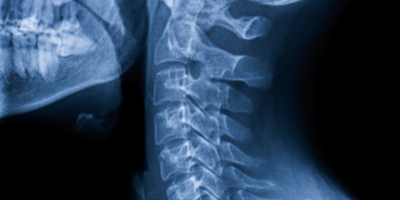

NACTN supports a network of clinical centers as well as clinical coordinating, data management and pharmacology sites, all dedicated to establishing best practices in the care and treatment of spinal cord injury. These sites have medical, nursing and rehabilitation personnel who are skilled in the evaluation and management of spinal cord injury. In addition to translating discoveries from the lab into clinical studies, NACTN maintains a patient registry of information that is important to the design and testing of possible new treatments for SCI.